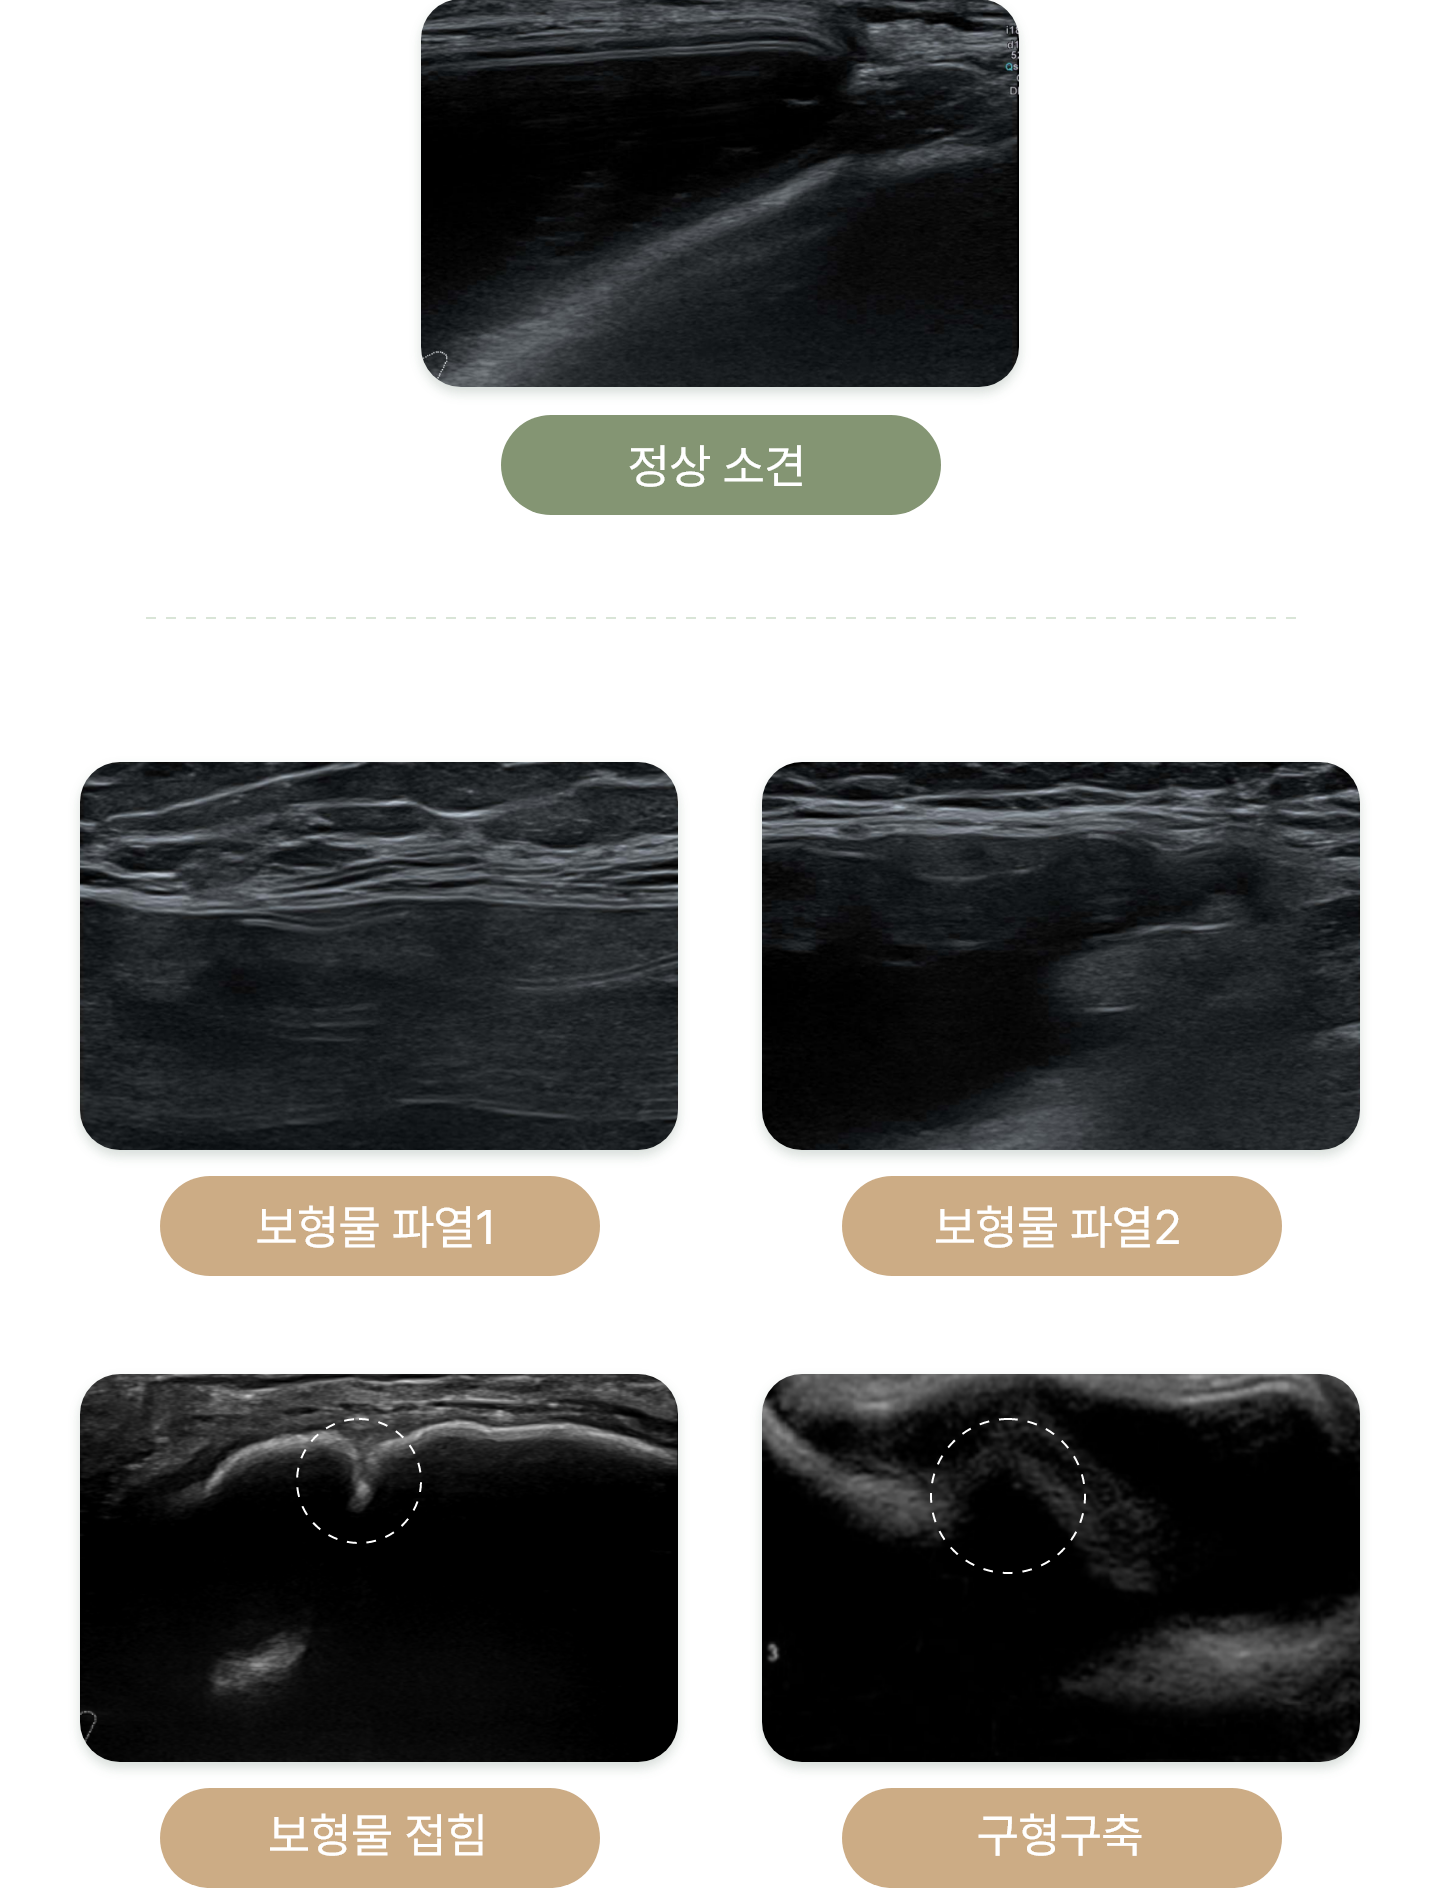

유방 초음파를 통해

확인 가능한 진단

보형물 수술 후 검진은 보형물의 위치,파열/접힘 여부,

보형물로 인한 증상 등 보형물 상태 파악이 중요합니다.

보형물 수술 후 검진은 보형물의 위치,파열/접힘 여부, 보형물로 인한 증상 등 보형물 상태 파악이 중요합니다.